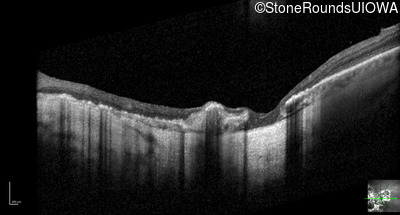

Optical Coherence Tomography - Right - 20/160 -2

Exemplar / OCT Stack